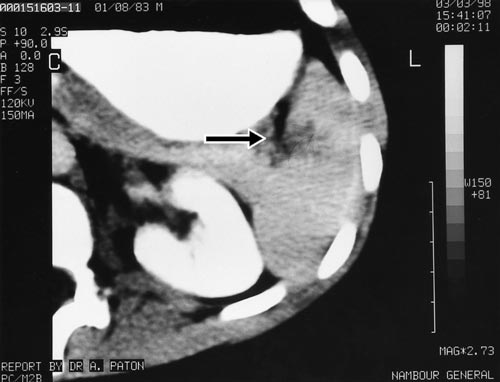

On presentation, six hours after the injury, he was pale and in pain. His pulse was 120/minute and blood pressure was 110/60 mmHg. He had marked tenderness in the left upper abdominal quadrant with guarding. A computed tomography (CT) scan of the abdomen revealed a full-thickness laceration of the spleen, extending into the hilum (Box 1).

The patient was managed by active observation, and did not require surgery or blood transfusion. Subsequent scans revealed healing of his injury by three months.